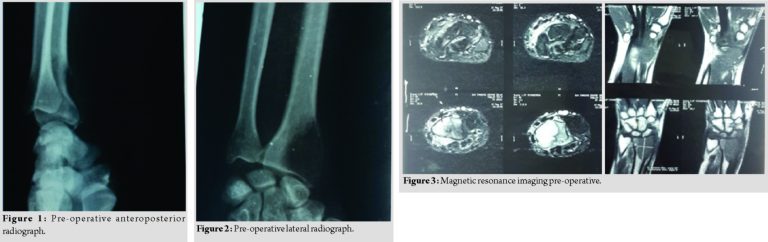

Pre-operative anteroposterior (AP) (Fig. 1) and lateral radiograph (Fig. 2) of the wrist were done which revealed an expanded osteolytic lesion at the epiphyseal region of the distal radius. Magnetic resonance imaging (MRI) (Fig. 3) and fine-needle aspiration cytology were done and GCT was diagnosed Campanacci Type 3. The patient was operated and treated by excision of tumor and reconstruction with contralateral fibular grafting with K-wire fixation of DER and biopsy of growth was sent. Above elbow slab was applied (Fig. 4 and 5).